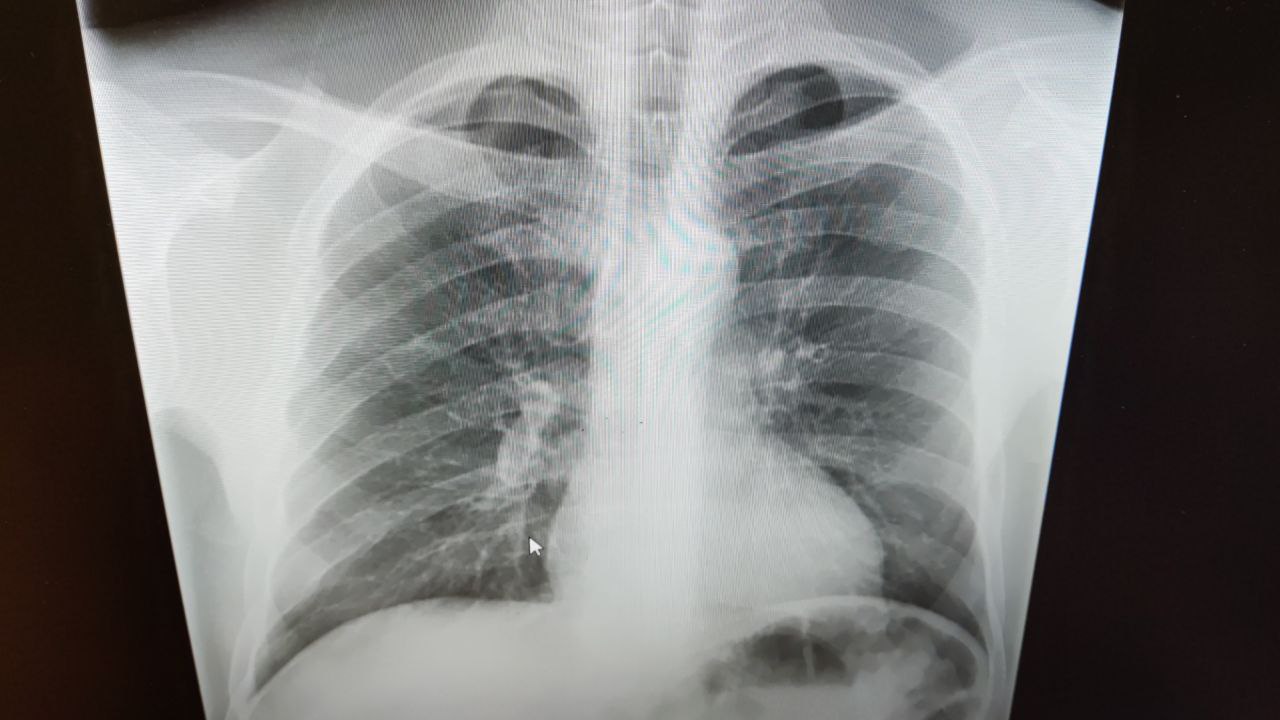

Gleb in Radiology/Рентгенология Чат

М45 лет, жалоб нет. Дыхание ослабленное, хрипов нет. Подскажите пожалуйста, что может быть